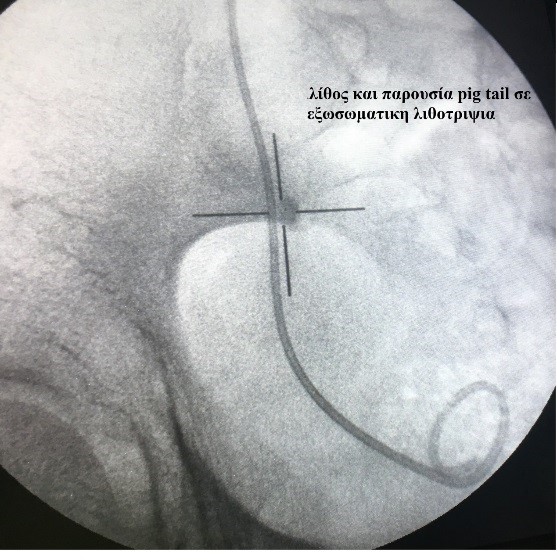

- Εξωσωματική λιθοτριψία Λίθοι μέχρι 1,5 εκατοστό είναι υποψήφιοι για εξωσωματική λιθοτριψία, μία μέθοδο ανώδυνη χωρίς την ανάγκη αναισθησίας και μη επεμβατική με καταγεγραμμένα μεγάλα ποσοστά θραύσης των λίθων. Η στόχευση των λίθων γίνεται με ακτινοσκόπηση ή με την βοήθεια υπερήχων.

|